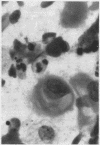

Fifty eight lung tumours were typed according to the second World Health Organization histological classification and compared with the cytological appearances obtained by fine needle aspiration in a total of 47 primary non-small cell carcinomas. The presence of glands, cell balls, branching or papillary structures, cylindrical cells and nuclear grooving were major diagnostic indicators for adenocarcinoma. Cytoplasmic macrovacuoles were more common in adenocarcinomas (69%) than in squamous (37%) and large cell (50%) carcinomas. Two or more of these features were combined in all well and moderately differentiated adenocarcinomas and in 67% of poorly differentiated adenocarcinoma. The major cytological indicators for squamous carcinomas were the presence of keratin and eosinophilic spindle cells with glassy or laminated cytoplasm. Granular cytoplasm was not specific for any histological type. A combination of the major features for both adeno- and squamous carcinoma was present in 58% of adeno-squamous carcinomas, including some poorly differentiated types. Correct typing could be obtained in almost all the well and moderately differentiated carcinomas and in about two thirds of the poorly differentiated tumours using FNA, provided that combinations and not individual variables are considered.